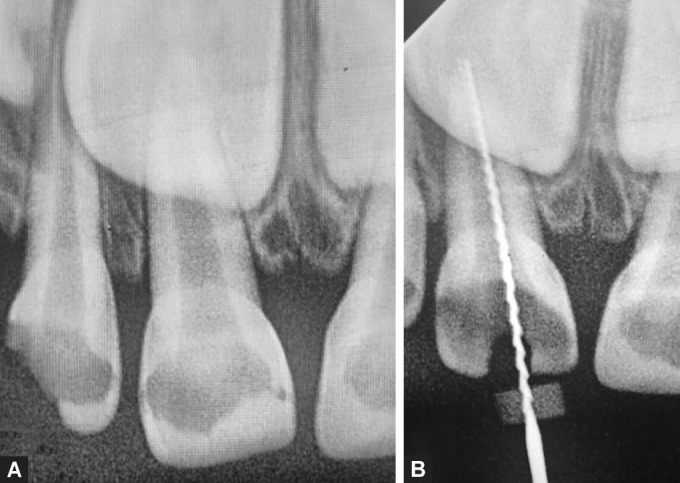

Materials and methods: About 42 children requiring pulpectomy in nonvital primary anterior teeth were divided into three groups. In the control group, teeth were irrigated with 3% NaOCl using a conventional needle irrigation (CNI) system. In experimental group I, 0.5% MTDZ and a CNI system were used, and in experimental group II, 0.5% MTDZ irrigant was used with the PATS. Samples were collected before and after cleaning and shaping of canals using paper points. The samples were incubated at 37°C for 24 hours on bile esculin agar, and colonies of Enterococcus species were counted.